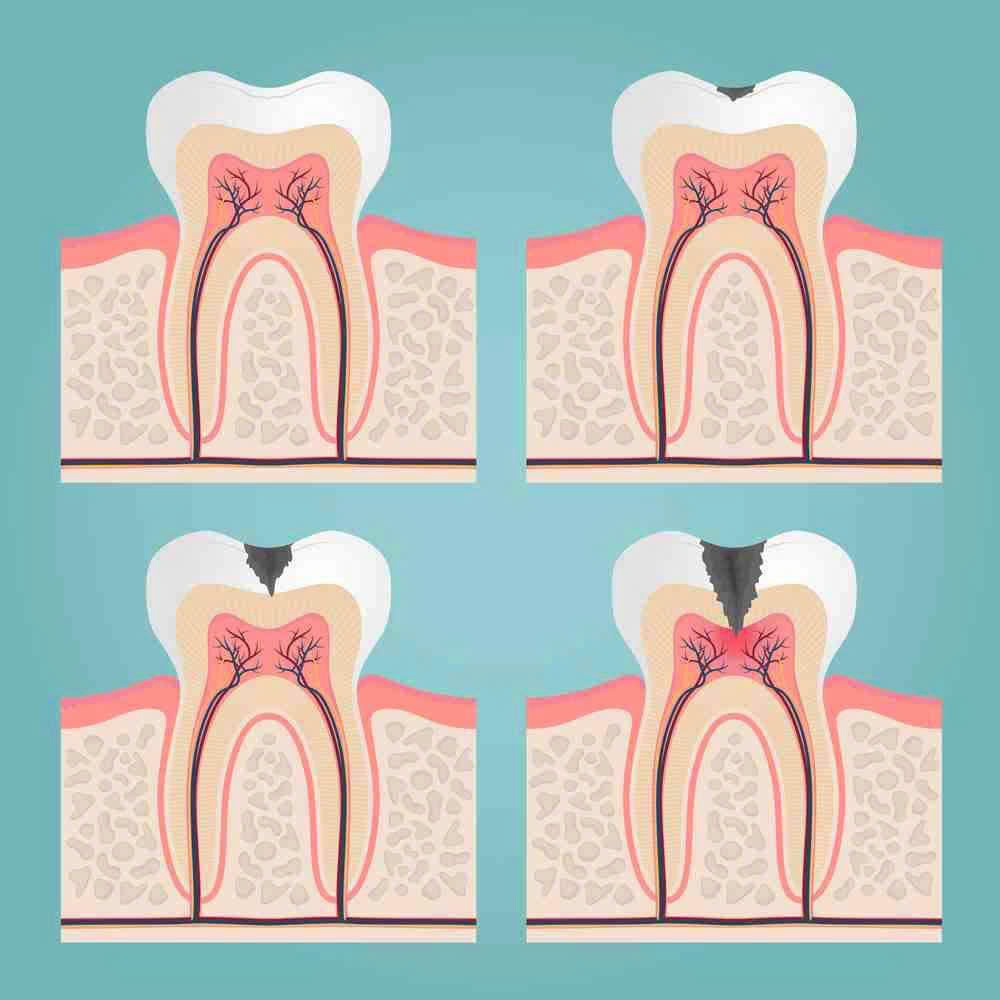

🔹 Diễn tiến của sâu răng dẫn đến viêm tủy

-

Sâu men: Tổn thương chỉ ở lớp men, có thể trám đơn giản.

Sâu ngà: Vi khuẩn ăn sâu hơn, gây ê buốt khi ăn uống.

Viêm tủy: Vi khuẩn xâm nhập vào buồng tủy, gây đau nhức dữ dội, nhất là ban đêm.

Hoại tử tủy: Tủy chết, nhiễm trùng lan ra xương hàm, gây sưng mặt, áp xe, thậm chí mất răng.

👉 Vì vậy, răng sâu không điều trị kịp thời rất dễ phải điều trị tủy để “cứu răng thật”.